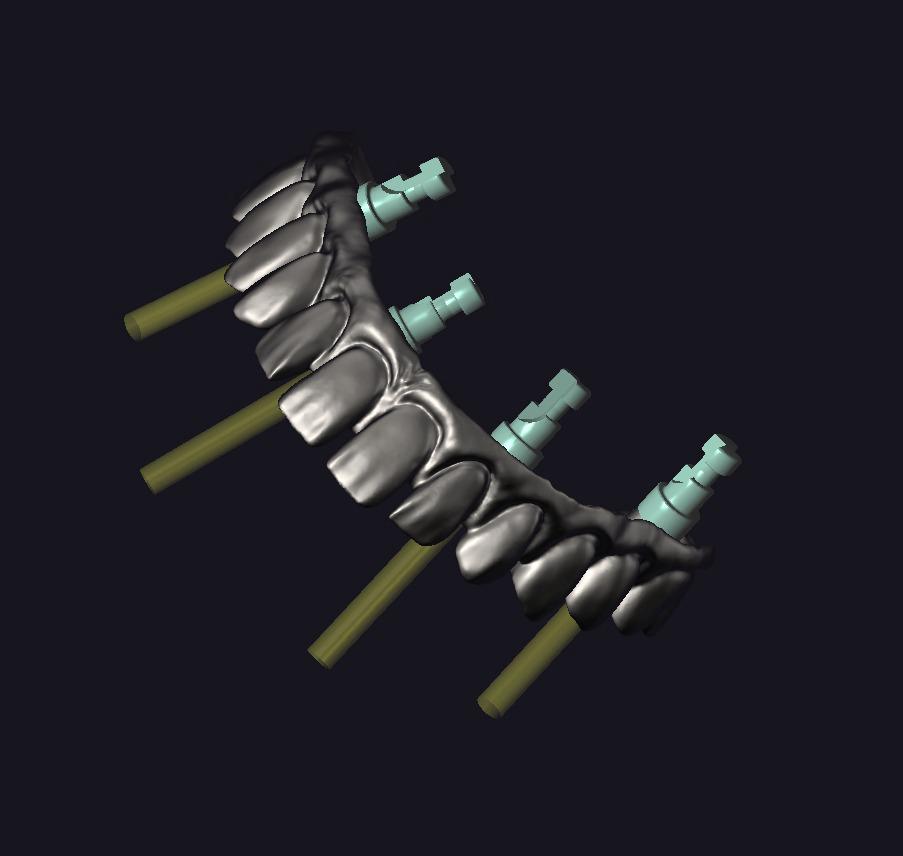

IMPLANT USTU ZIRKONYUM

IMPLANT USTU ZIRKONYUM ALT YAPI

MONOLITIK IMPLANT USTU ZIRKONYUM & ÜSTTEN ViDALI ZİRKONiUM

MULTILAYER IMPLANT ÜSTÜ ZIRKONYUM & ÜSTTEN VİDALI ZIRKONYUM